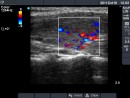

First examination (first row):

Clinical presentation: A 29-year-old woman was referred for evaluation of complaints suggesting hyperthyroidism. She had no eye signs.

Palpation: Both lobes were enlarged. No nodule was palpable.

Ultrasonography: Both lobes were enlarged, moderately hypoechogenic, inhomogeneous and displayed increased vascularization.

Diagnosis: Graves' hyperthyroidism.